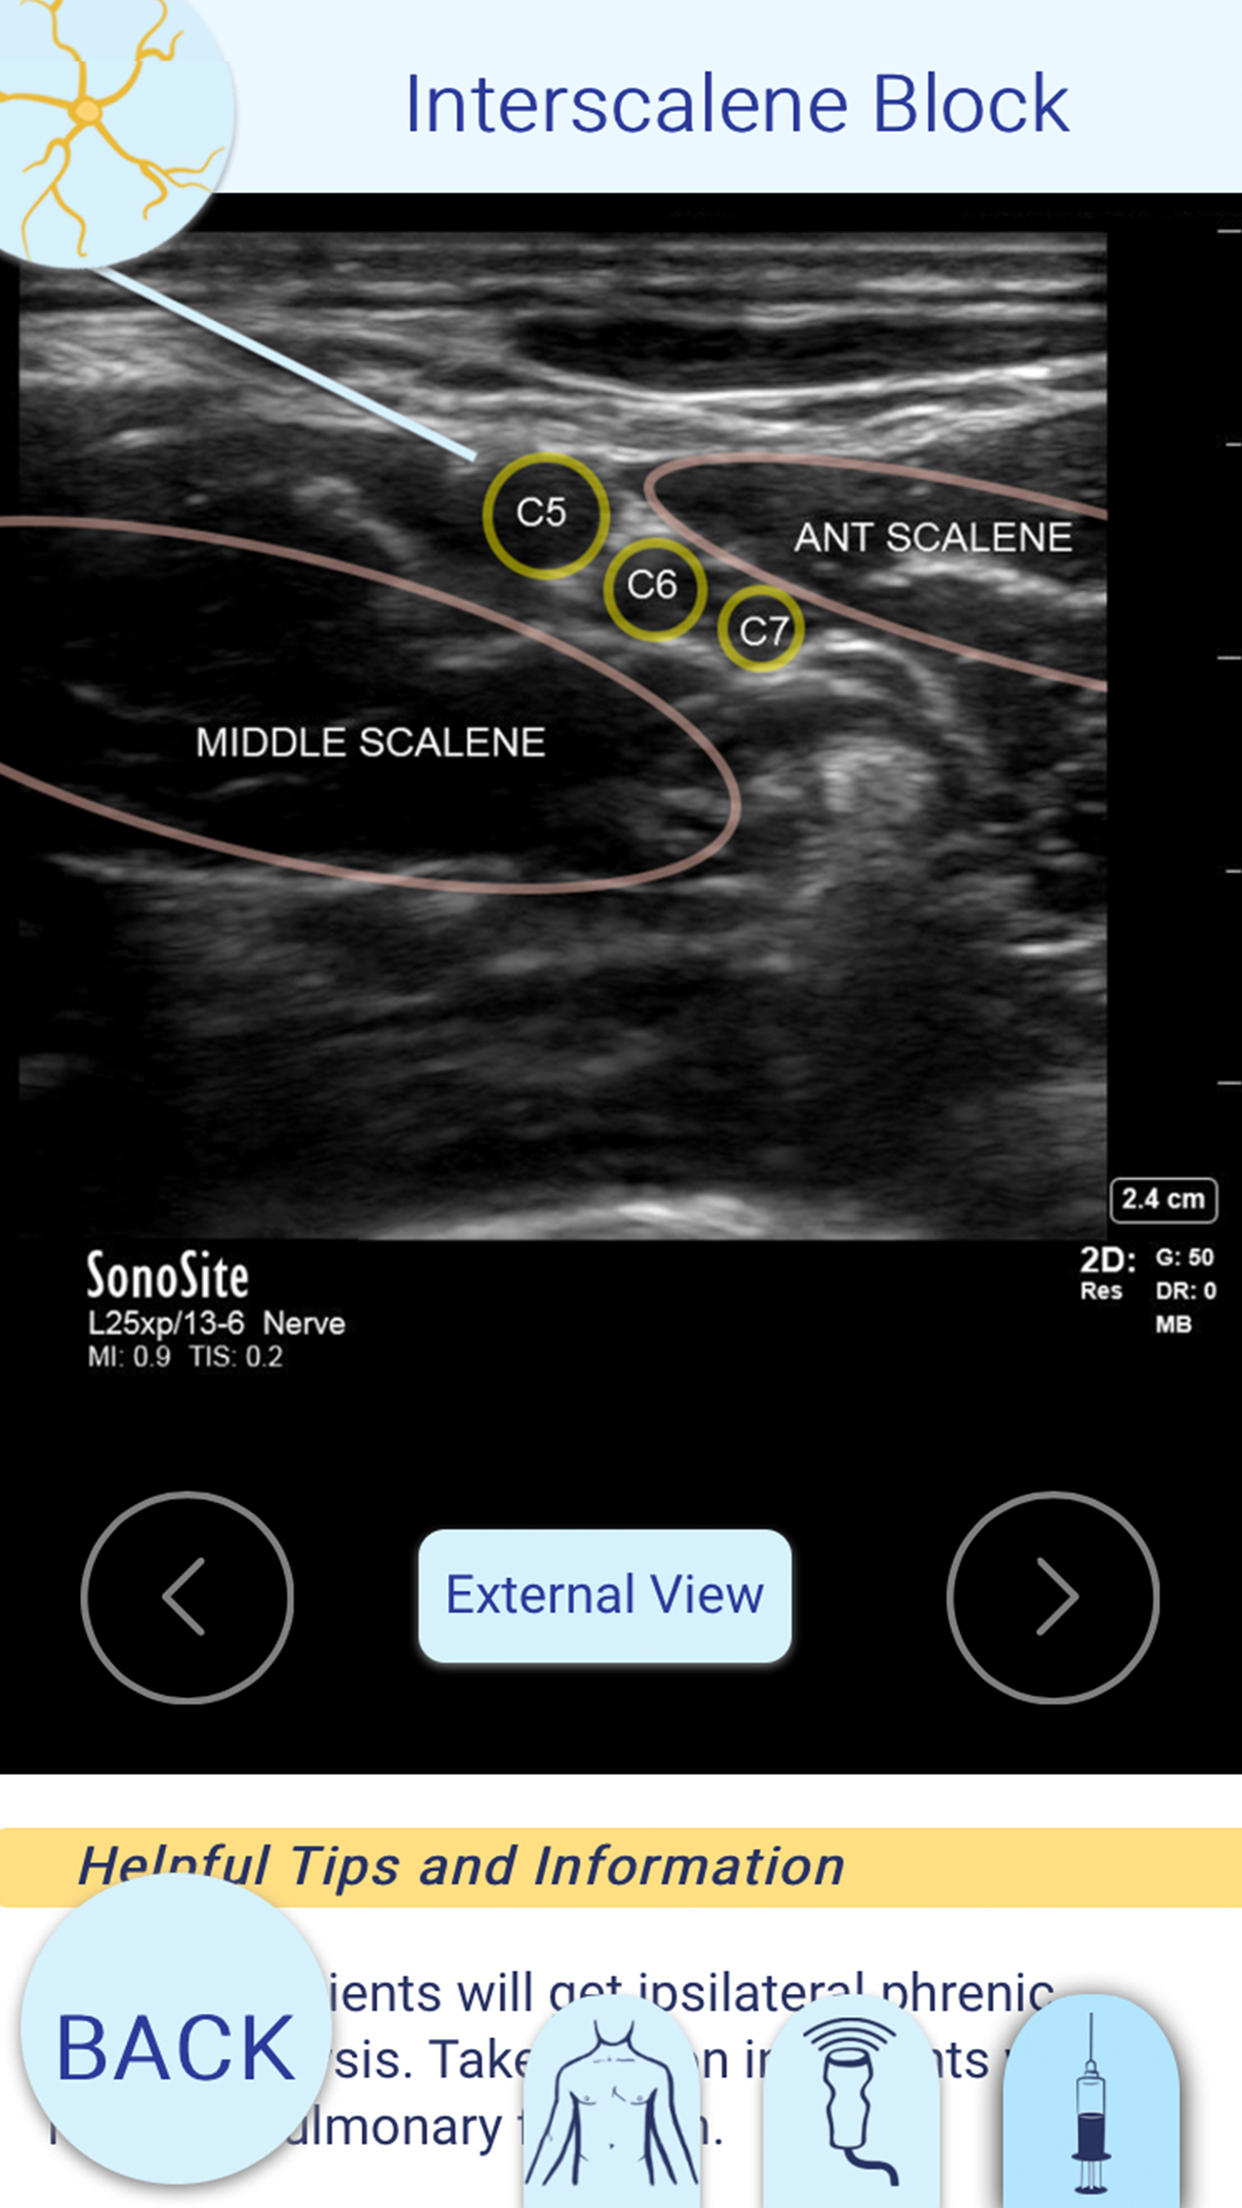

This app demonstrates how to complete different nerve blocks typically used in Emergency Medicine. It features a description about each block, photos of injection sites and angles, ultrasound views of target nerves and surrounding anatomy, as well as helpful tips along the way. Sorting by injury, this app gives the ER physician a quick reference guide to performing the targeted nerve block. It also features a "library" of common local anesthetics and their dosing properties.